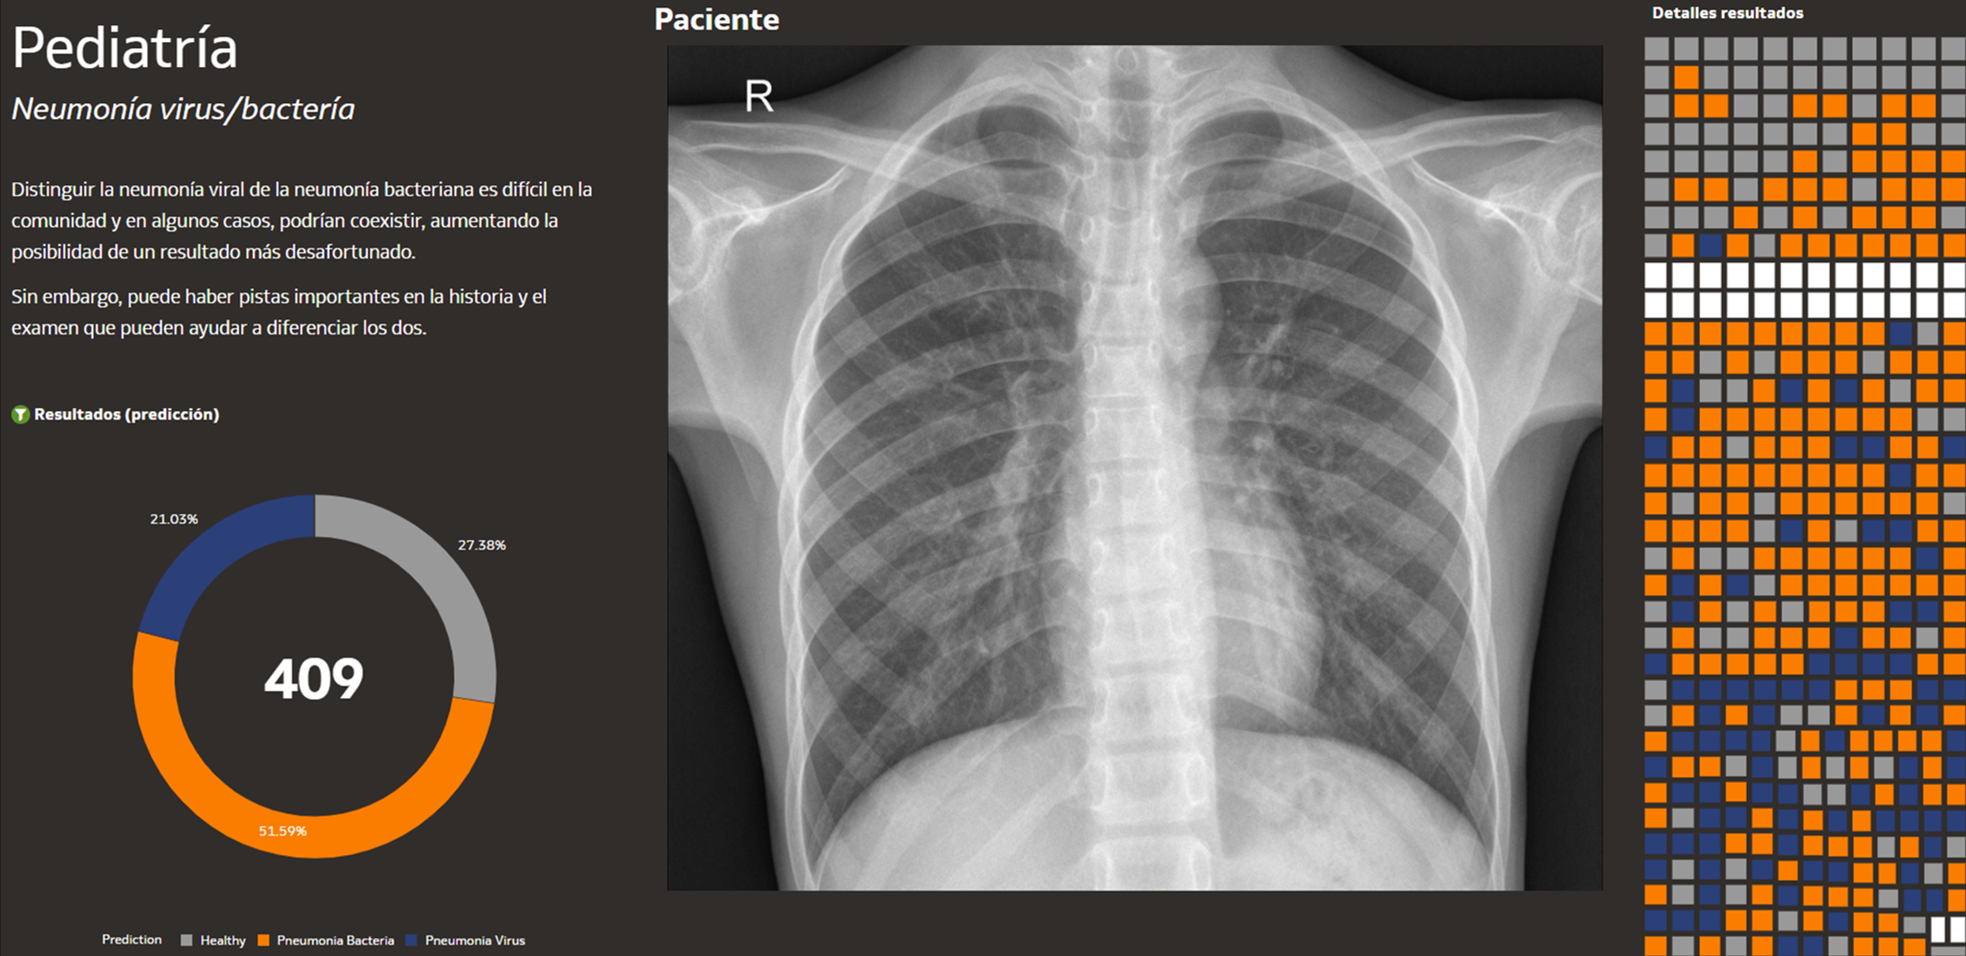

Image of community example showing music sales Image of community example showing a brain MRI Image of community example showing most expensive US metro areas Image of community example showing passport analytics Image of community example showing ROI with active learning Image of community example showing US national parks Image of community example showing cheapest ways to get protein Image of community example showing bank customer churn Image of community example showing pediatria